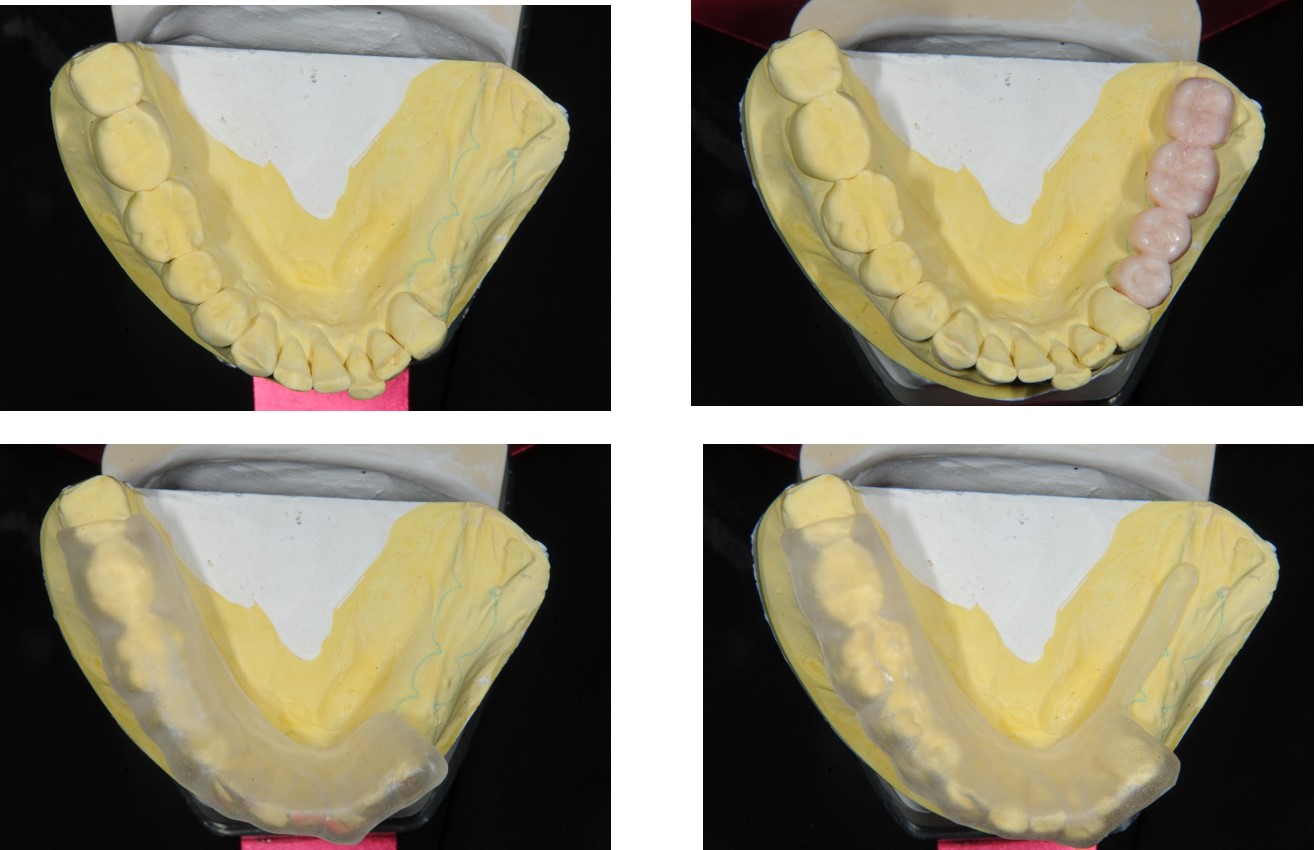

▼(下圖為蠟型復形,與電腦定位器,原來模型是這樣用的!)

蠟型復形,與電腦定位器

ImplantMax手術模板

臨時假牙塑形:#34-37